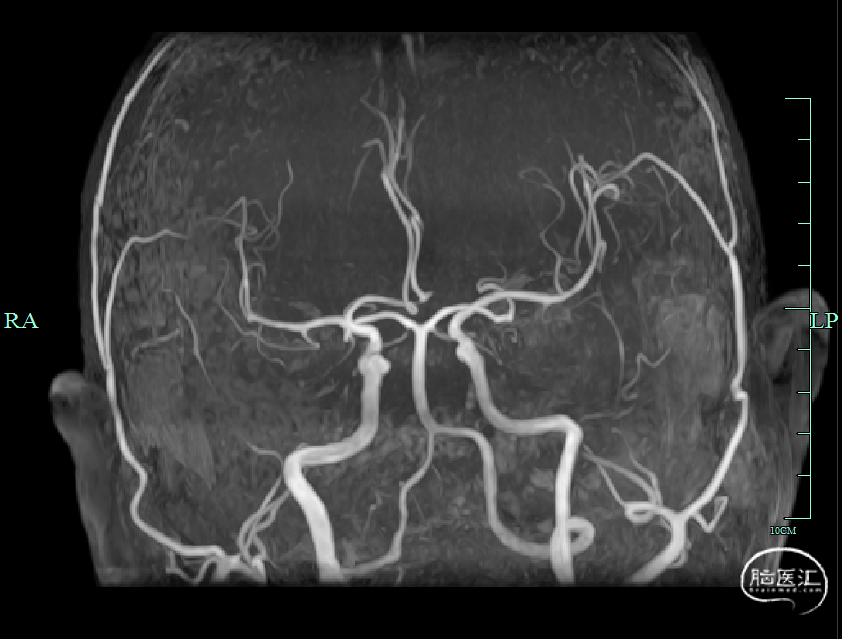

➤术后影像

术后第一天,头颅DWI可见尾状核及基底节区新发脑梗死;MRA可见右侧颈内动脉、右侧大脑中动脉、双侧大脑前动脉无再次闭塞。